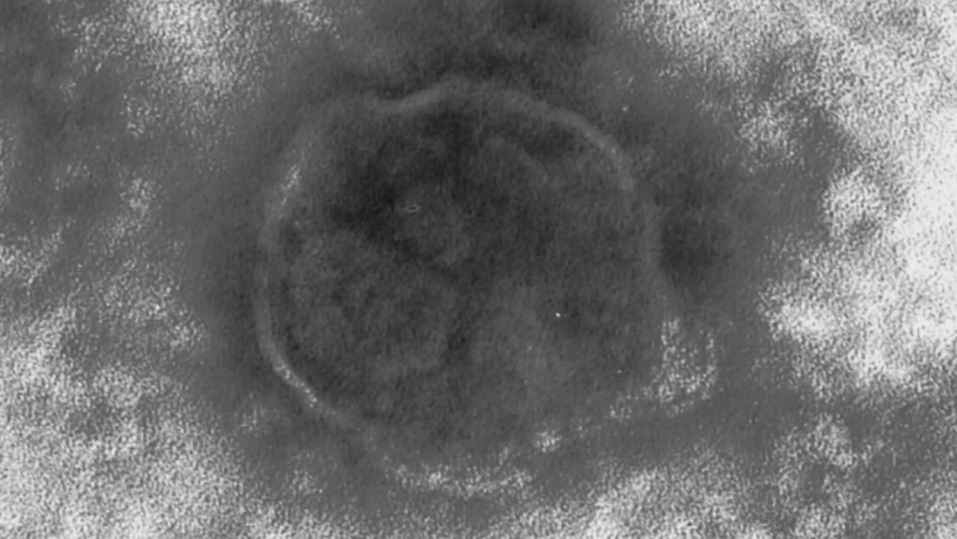

提供:東京都健康安全研究センター